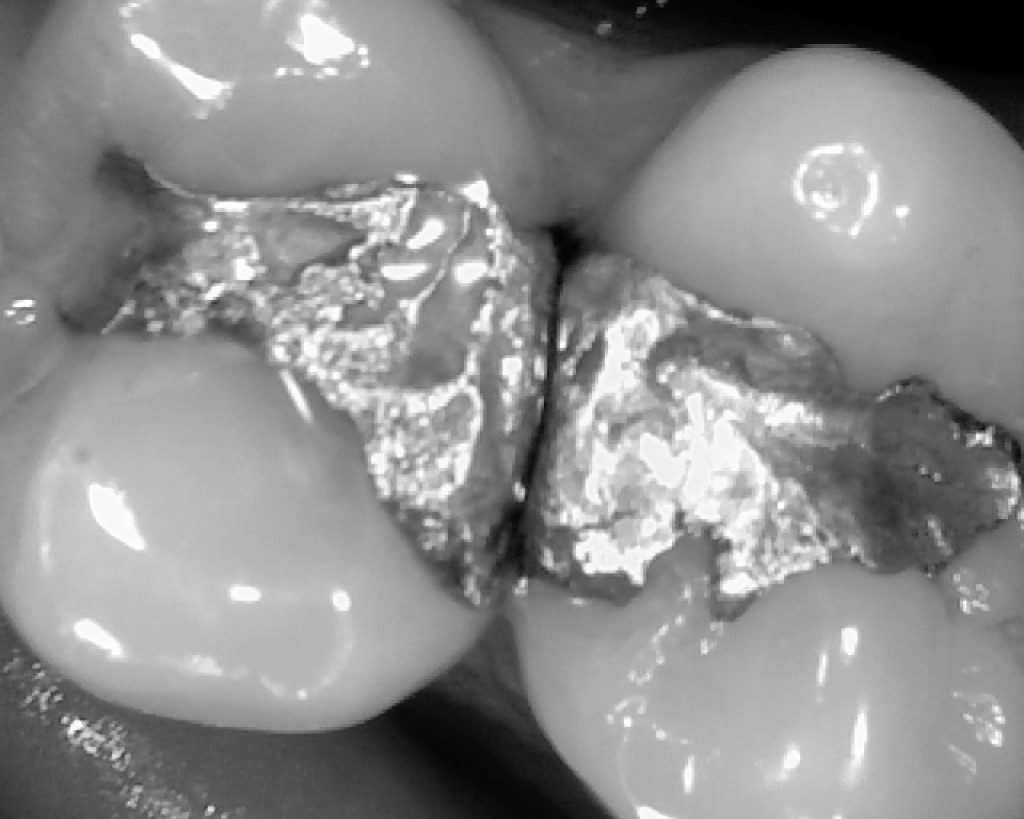

Ms. Indermuhle had her fillings placed by a biological dentist with the NHS General Dental Services. NHS holds that amalgam fillings are safe and regulations prefer amalgams for use on back teeth. That mercury fillings are safe is a view held by many government health services around the world. She contacted the NHS and received a letter expressing sympathy, but the NHS has not admitted any kind of responsibility for her health issues. She was given contact information for the NHS Ombudsman, but the Ombudsman typically does not review cases more than a year after a problem becomes apparent.